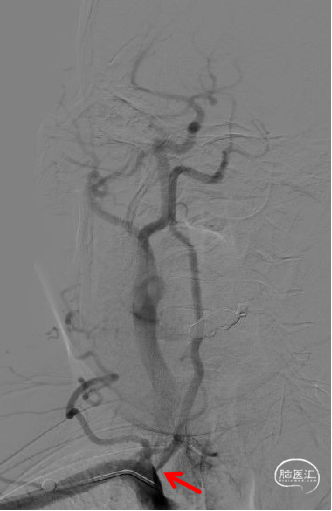

术前脑血管造影示:右侧椎动脉V1段重度狭窄。

患者取平卧位,常规消毒术区皮肤,置无菌单,右侧桡动脉局麻后,行右侧桡动脉Seldinger法穿刺,并置入6F动脉鞘,以180cm超滑泥鳅导丝携单弯管行选择性脑动脉造影。造影结果示:右侧椎动脉V1段重度狭窄。

术前影像